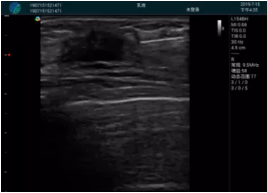

腺體內(nèi)部清晰顯示一低回聲塊影,形態(tài)不規(guī)則,邊界模糊,邊緣呈毛刺狀,內(nèi)部見砂礫樣鈣化

M20引導(dǎo)下穿刺活檢術(shù)

M20引導(dǎo)下平面內(nèi)穿刺取出的腫塊組織